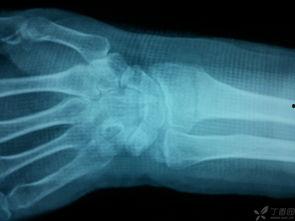

首先,让我们来了解一下什么是骨科手法复位。骨科手法复位,顾名思义,就是通过医生或专业人士的手法,对骨折、脱臼等骨科疾病进行复位的一种治疗方法。这种方法不仅能够减轻患者的痛苦,还能在一定程度上避免手术的风险。